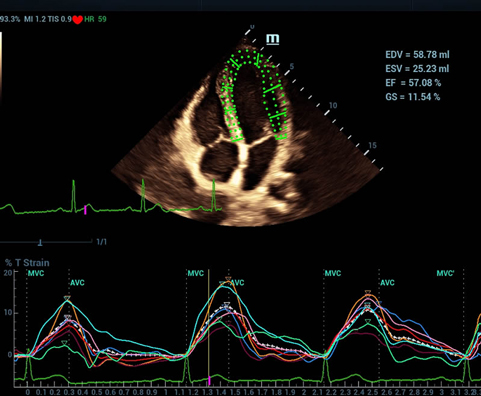

Resona 7 — качество изображений уровня премиум и новые клинические возможности. Система V Flow теперь способна не только оценивать гемодинамические показатели с частотой 600 кадров/сек, но также обеспечить интеллектуальное получение из 3D данных наиболее важных проекций для диагностики ЦНС плода.

Обеспечивая качество изображения уровня премиум, Resona 7 также повышает клинические возможности исследования при помощи революционной системы V Flow, предназначенной для оценки гемодинамических показателей сосудов; обеспечивает интеллектуальное получение из 3D данных наиболее важных проекций для диагностики ЦНС плода. Сочетая в себе интуитивно понятное сенсорное управление с распознаванием жестов и все важные клинические характеристики, передовая система Resona 7 настоящая новая волна в сфере ультразвуковых инноваций.Благодаря перечисленным выше характеристикам, Resona 7 является доступным решением премиум-класса, которое удовлетворяет высоким требованиям клинической точности и эффективной диагностики в условиях современной перегруженной больничной среды.

Echo Boost™ - режим улучшенной визуализации структур сердца

-